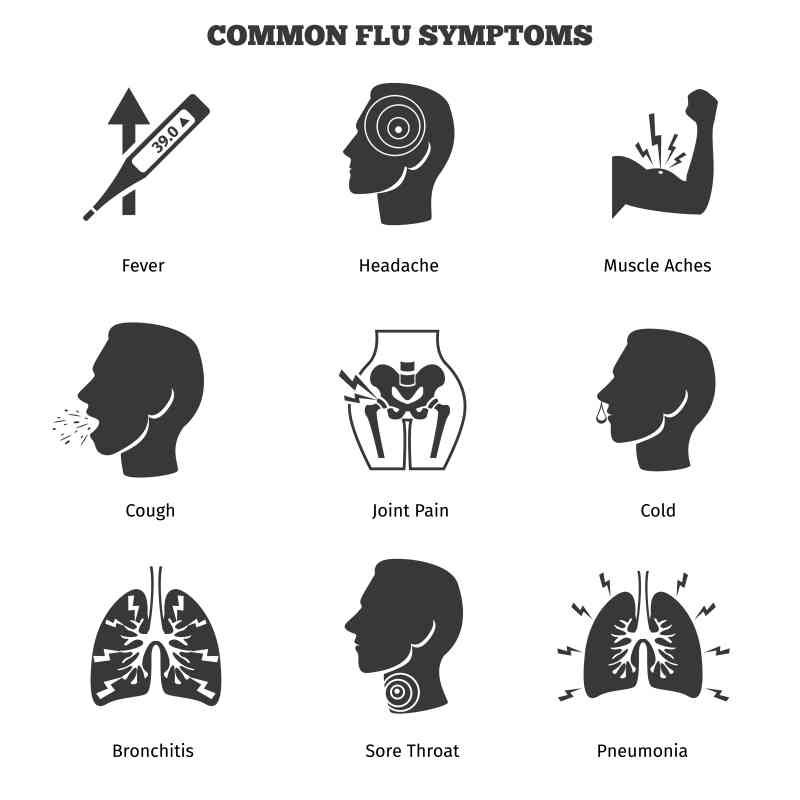

Flu-Like Symptom: There are certain flu-like symptoms that you might feel if you are going to have a heart attack. Some of the symptoms include fatigue, chest pain, and fever. They can last anywhere between 2-10 days.